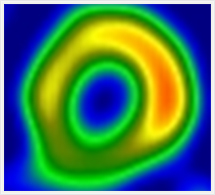

安静時心筋血流シンチグラフィ

心臓の筋肉に酸素や栄養を供給する冠動脈が狭窄または閉塞すると、心臓は虚血状態になり、心筋梗塞に陥ります。心筋細胞の状態(虚血部位、梗塞範囲)を調べる目的で行われる検査です。

1.前準備として食事・水分の制限は特に必要ありません。

2.心筋血流シンチグラフィ用の検査薬を静脈注射します。

3.検査薬が心臓の筋肉に集まるのに約30分かかるため、注射後30分経てから撮影を開始します。

4.検査薬は肝・胆道系から排泄されるため、妨げにならないように検査開始直前に必ず水分を少し摂取していただきます。

5.撮影時間は約30分かかります。

6.健康な心臓の筋肉には通常良く集まり、障害がある場合はその障害の程度に応じた集積の低下がみられます。